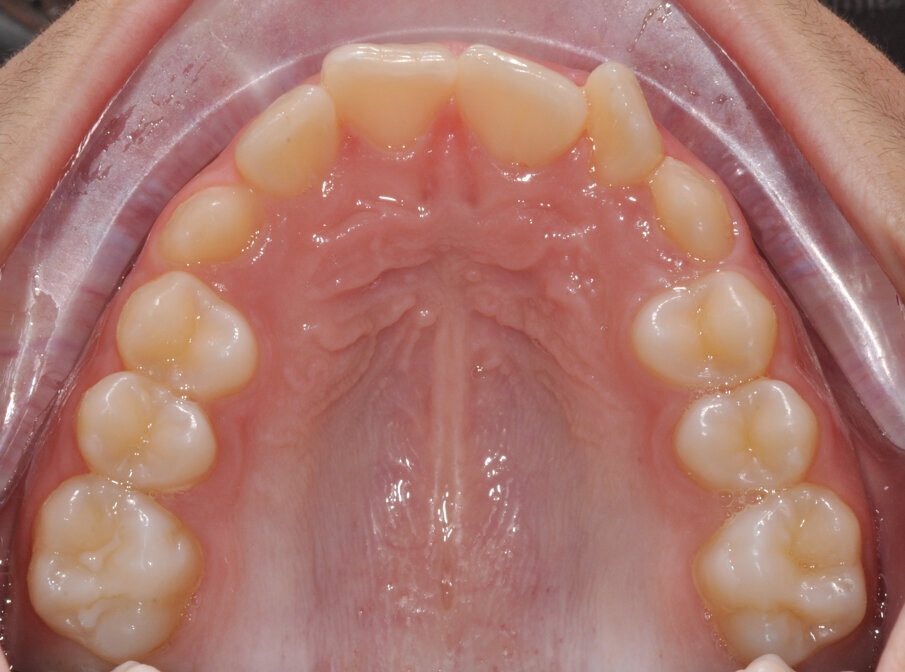

Al termine della terapia si può vedere una normalizzazione della permuta (Fig. 10) con la corretta comparsa in arcata dei canini permanenti al follow-up di 1 anno (Fig. 11).

Fig. 11_Follow-up 1 anno.